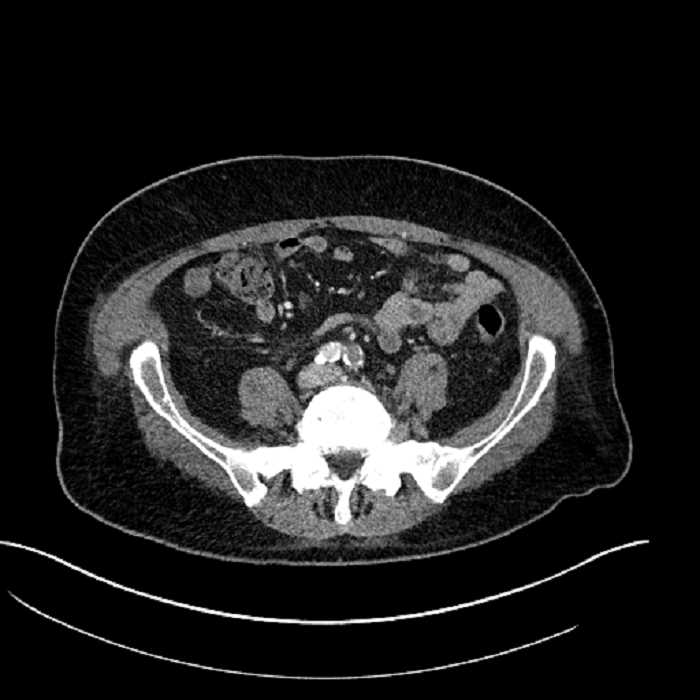

Age: 63

Sex: Male

Indication: Abdominal pain

• Mild mural thickening of a segment of the sigmoid colon with adjacent fat stranding and a 1.5 cm fluid and gas collection along the tip of an inflamed diverticulum

• Loss of the normal fat plane between this collection and adjacent loops of small bowel, which demonstrate mural thickening

• No bowel obstruction

Acute sigmoid diverticulitis complicated by a small contained perforation and a large abscess in the right hepatic lobe. Additional small subcapsular abscesses along the anterior margin of the left hepatic lobe.

Additionally, loss of the normal fat plane between the peridiverticular collection and adjacent thickened loops of small bowel raises the potential for an enterocolonic fistula.

Hepatic abscess showing the double target sign with low density internally surrounded by a thin inner enhancing rim (red arrow) and ill-defined outer low density rim (yellow arrow). Blue arrow indicates an internal septation. Red arrows: additional smaller subcapsular abscesses. Red arrow: focal contained perforation associated with diverticulitis.